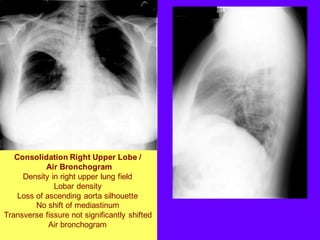

Consolidation Right Upper Lobe /

Air Bronchogram

Density in right upper lung field

Lobar density

Loss of ascending aorta silhouette

No shift of mediastinum

Transverse fissure not significantly shifted